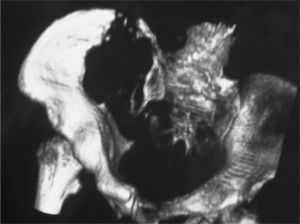

Mujer de 88 años diagnosticada de enfermedad de Paget en pala ilíaca derecha desde hacía un año sin necesidad de tratamiento. Acude a urgencias por dolor en la cadera derecha, de 3 meses de evolución, que empeora con el movimiento, la despierta por la noche y no cede con analgésicos habituales. La exploración sistémica y neurológica fue normal y en el aparato locomotor se objetivó dolor a la palpación y limitación a la movilización activa y pasiva de la cadera derecha en todos los planos, sin aumento de partes blandas. El estudio hematológico, bioquímico y de metabolismo óseo fue normal, con proteína C reactiva (PCR) y velocidad de sedimentación globular (VSG) normales y con fosfatasa alcalina (FA) de 130 (normal, 20-140) U/l. La radiografía simple de pelvis puso de manifiesto una lesión lítica de gran tamaño en el seno de un hueso pagético en pala ilíaca derecha con destrucción cortical y fracturas (fig. 1). Se realizó una tomografía computarizada (TC) de pelvis y caderas que confirmó la presencia de una lesión lítica con gran destrucción ósea, indicativa de osteosarcoma (fig. 2).

La biopsia de la lesión fue compatible con osteosarcoma. La gammagrafía ósea mostró que la lesión estaba localizada, sin afectar a otras estructuras. La paciente, al no ser candidata a tratamiento quirúrgico por su edad y la localización de la lesión, pasó a cuidados paliativos para control del dolor. Murió a los 6 meses por descompensación de insuficiencia cardíaca.